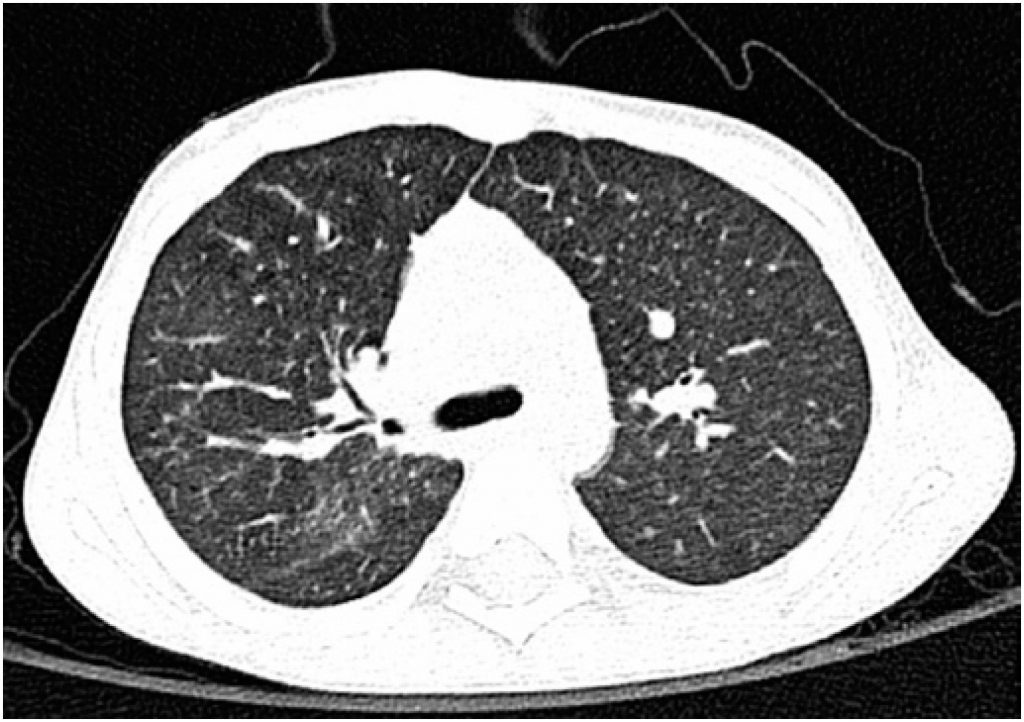

Idiopathic pulmonary hemosiderosis is a potentially fatal disease that results from episodes of alveolar hemorrhage of unknown origin. The clinical spectrum is varied, and anemia may constitute the only manifestation of illness, preceding other signs and symptoms by several months. We present the case of a 4 year-old child presenting with fever, vomiting and prostration, associated with pallor. He had microcytic and hypochromic anemia refractory to iron therapy. Gastrointestinal bleeding was ruled out after negative extensive etiological investigation. Subsequently, pulmonary infiltrates suggestive of alveolar hemorrhage were observed in the chest radiography. The cytological exam of the bronchoalveolar lavage showed hemosiderin-laden macrophages. After the etiological study, the diagnosis of idiopathic pulmonary hemosiderosis was made by exclusion. He was initiated on corticosteroid therapy, later associated to an immunosuppressive agent, with subsequent correction of anemia and of the radiological pattern. The patient is currently asymptomatic.